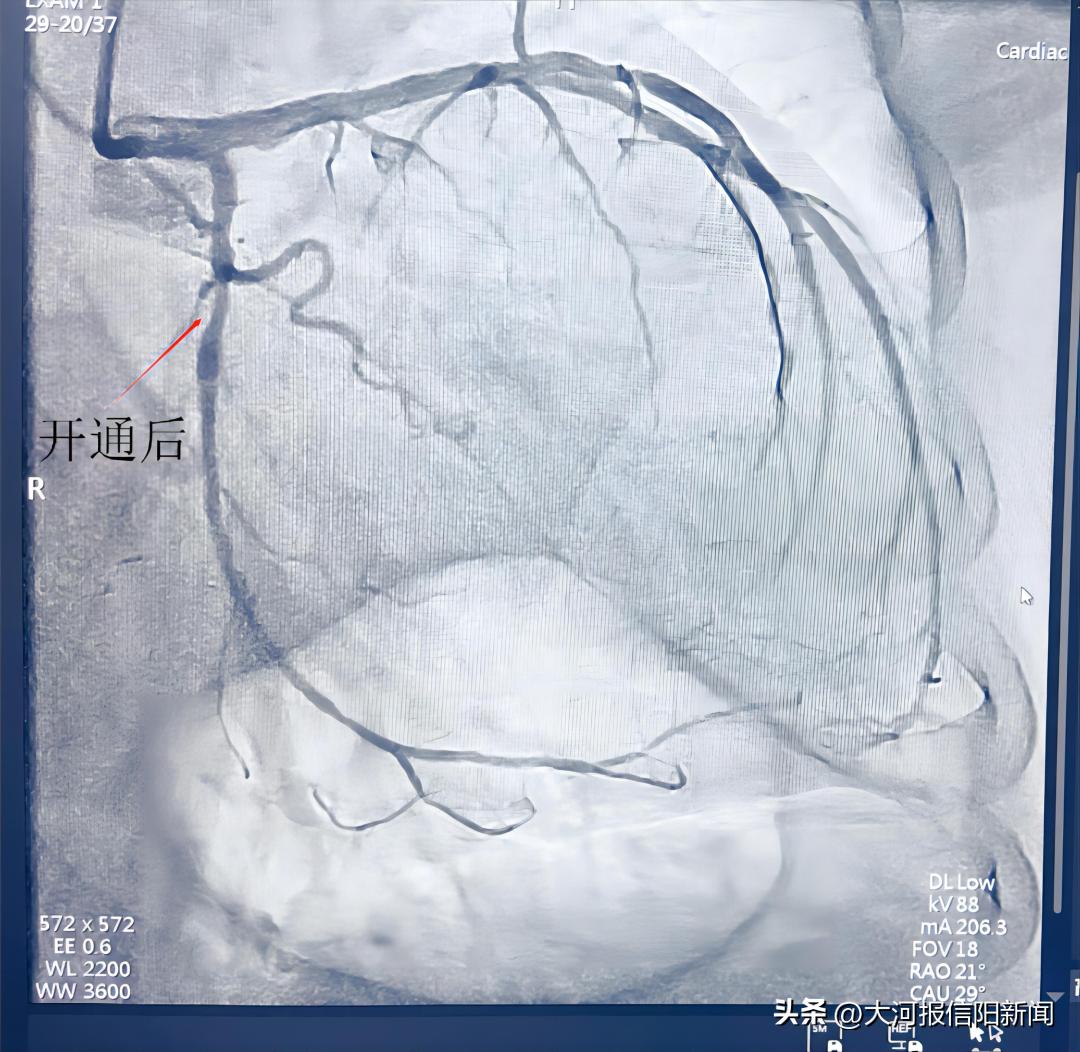

患者陈某,女,65岁,以“间断胸闷气短1月与”来我院就诊,经行冠状动脉造影,提示患者回旋支中段闭塞,术中征得家属同意后,决定开通闭塞血管,经过2个小时不懈努力,终于开通回旋支闭塞血管,术后患者安全返回病房。